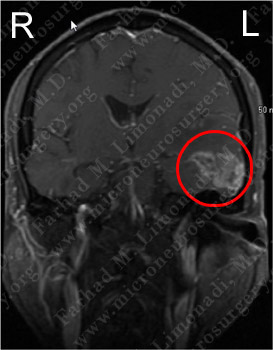

Imaging

MRI scan of the patient's brain showed a left temporal brain tumor.